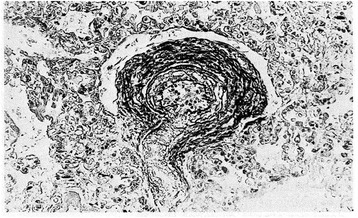

Figure 8.

Pulmonary arteriole from a 11-day-old infant who died from severe perinatal asphyxia. Marked thickening of medial muscle mass is evident (PAS-Gieson stains). From Distefano G et al. [12] Med Surg Ped 1992. (Personal observation).